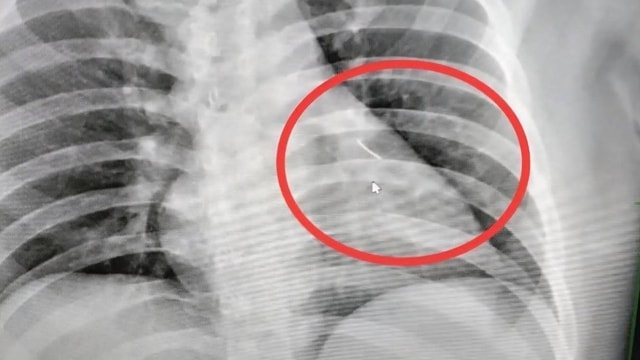

Sau khi chụp X-quang, các bác sĩ phát hiện một cây kim dài 7 cm mắc kẹt trong ngực của người đàn ông, gần như đâm xuyên tim.

Nhân viên bệnh viện đã chụp X-quang và phát hiện một vật thể nhỏ sắc nhọn bên trong cơ thể ông, gần tim. Vật thể này sau đó được xác định là một cây kim dài khoảng 7 cm. Ông Boonlert sau đó được chuyển đến Bệnh viện Buriram để phẫu thuật, các bác sĩ mô tả ca phẫu thuật này phức tạp và có rủi ro cao.